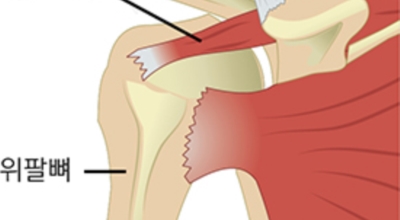

회전근개 증후군은 회전근개에 변형과 파열이 생긴 질환을 말합니다. 회전근개란 어깨와 팔을 연결하는 4개의 근육(극상근, 극하근, 소원근, 겹갑하근) 또는 힘줄로 이루어져 있는 것으로 보입니다. 어깨 근육통을 막연히 오십견으로 알고 방치하다가 치료 시기가 늦어지는 경우가 있답니다. 적절한 시기에 병원에 가는 것이 필요합니다.

상완골두 즉 상완을 구성하는 뼈가 높아져 견봉과 맞닿으면서 뼈끼리 닿아서 관절염이 될 수 있답니다. 최악의 경우 파열이 왔는데 방치하면 탈구로 이어질 수 있기 때문에 조심해야겠습니다. 세팔을 위로 뻗기가 힘듭니다. 본인 스스로가 팔을 못 들어 올리는 상태가 되는데, 다른 사람이 올려주면 올릴 수 있지만 손을 떼어버리면 힘이 빠져서 팔을 떨구게 되어요.